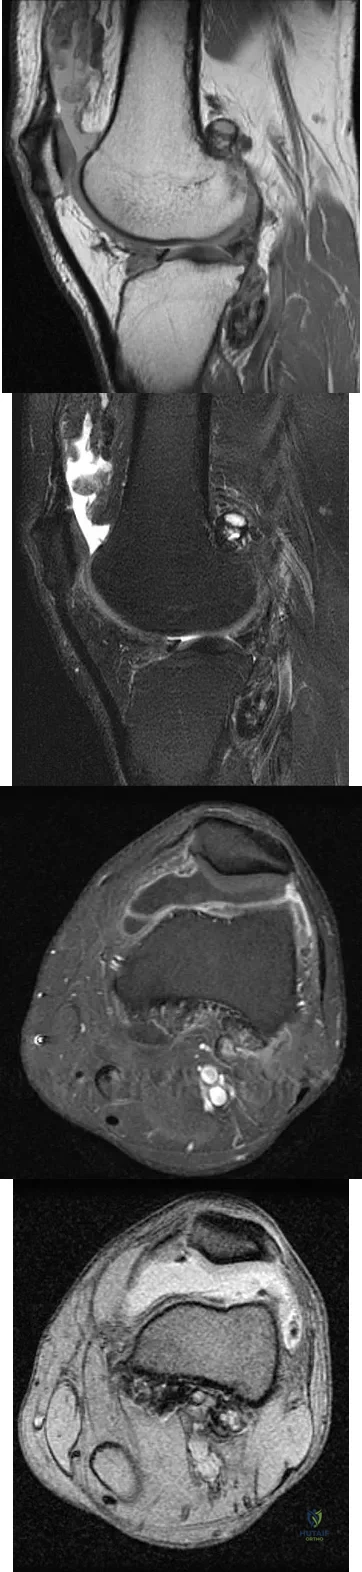

A 28-year-old man reports knee stiffness, swelling, and a constant ache that is worse with activity. Examination reveals an effusion, global tenderness, and warmth to the touch. Flexion is limited to 110 degrees. Figures 48a through 48d show sagittal T1-weighted, sagittal T2-weighted, axial T1-weighted fat-saturated gadolinium, and axial gradient echo MRI scans. Based on these findings, what is the most likely diagnosis?

Explanation

The MRI scans show multiple low-signal intensity lesions scattered throughout the knee, extending posteriorly inferior to the tibial plateau. The low-signal intensity on both the T1- and T2-weighted images, the modest vascularity noted on the gadolinium image, and the "blooming" noted on the gradient echo image (ferrous-laden tissue) are all strongly suggestive of diffuse PVNS. Whereas synovial chondromatosis can present as diffuse masses in the knee, they present as nodule masses that have low T1- and high T2-weighted signal characteristics. Resnick D (ed): Diagnosis of Bone and Joint Disorders. Philadelphia, PA, WB Saunders, 2002, pp 4241-4252.